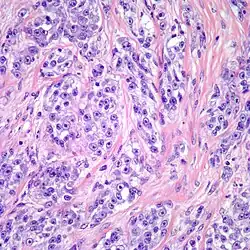

Clear cell sarcoma. Tumor cells with prominent nucleoli and clear cytoplasm are arranged in well-defined nests surrounded by dense fibrous stroma.

Despite the name clear cell sarcoma, the tumor cells do not necessarily need to have clear cytoplasm. The lesion has a distinctly nested growth pattern with a mixture of spindle, epithelioid and tumor giant cells. Approximately two thirds of the tumors contain melanin pigment. Clear cell sarcoma, similar to melanoma, has consistent positivity for S-100, HMB-45, and MITF.[6]